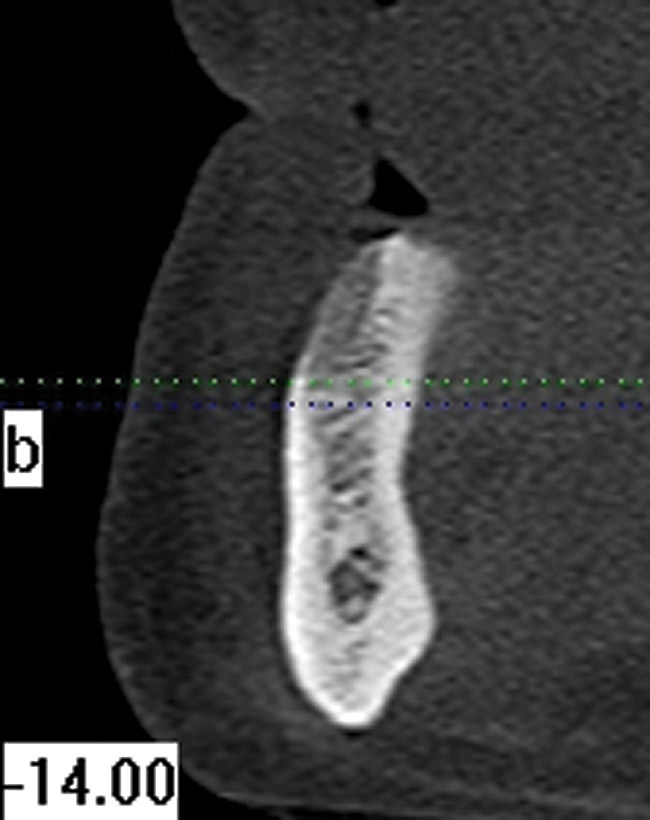

The use of cone-beam computed tomography (CBCT) has revolutionized clinical diagnostic abilities. Featuring advantages such as a relatively small size, less radiation exposure, and lower cost, CBCT has gained popularity by improving predictability and the quality of care in implant dentistry. This technology has value in aiding in the diagnosis of root fractures. Recently, a study found dental CBCT exhibited greater accuracy (62.8% versus 54.5%) in helping to diagnose vertical root fractures than conventional radiography. The investigators concluded that use of dental CBCT is effective for the diagnosis of root fractures regardless of the direction.3

CBCT has been available for craniofacial imaging since 1999 in Europe and since 2001 in the United States. The scanner uses a cone-shaped x-ray beam rather than a conventional linear fan beam to provide images of the skull's bony structures. CBCT uses a square 2-dimensional (2-D) array of detectors to capture the cone-shaped beam. Subsequently, reconstruction software is applied on the CBCT volumetric data to produce a stack of 2-D gray-scale level images of the anatomy.